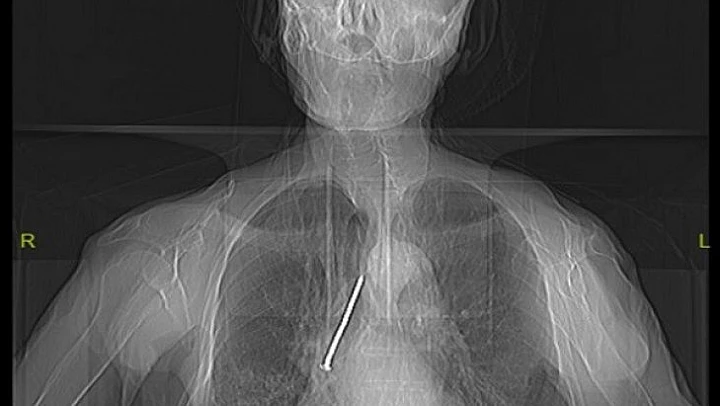

Soluk borusuna kaçan 10 santimlik çivi çıkarıldı

Elazığ'da, hastaneye başvuran 91 yaşındaki Keko Ateş'in nefes borusuna kaçan 10 santimetrelik inşaat çivisi, yapılan operasyonla başarılı bir şekilde çıkarıldı.

Elazığ'da, boynundan nefes borusuna açılan açıklık aracılığıyla solunumunu sağlayan Keko Ateş (91), öksürük ve nefes darlığı şikayetiyle Fethi Sekin Şehir Hastanesine başvurdu. Burada yapılan tetkik ve muayeneler sonucu yaşlı adamın nefes alıp verdiği boşluğu temizlemek için kullandığı 10 santimetrelik çivinin soluk borusuna kaçtığı belirlendi. Hayati tehlike oluşturan çivi, Göğüs Cerrahi Uzmanı Dr. Öğretim Üyesi Murat Kılıç tarafından “Rijit Bronskoskopi” işlemi ile çıkarıldı. Yaşlı adam çivinin çıkarılmasından kısa süre sonra hasta taburcu edildi.

Hızlı bir şekilde müdahale edilmediği takdirde hayatı tehlikeye atabilen bir durumla karşı karşıya kaldıklarını belirten Dr. Kılıç, "Larenks kanseri nedeniyle 24 yıl önce boynundan nefes borusuna açılan açıklık aracılığıyla nefes alıp verebilen hasta, nefes borusundaki bu açıklığı temizlemek amacıyla kullandığı 10 santimlik çiviyi soluk borusuna kaçırmış. Bu nedenle gelişen öksürük ve nefes darlığı şikayeti ile önce başka bir sağlık merkezine başvurmuş, ardından Fethi Sekin Şehir Hastanemiz Göğüs Cerrahisi Kliniğine yönlendirilmiş. Biz de hastanede 91 yaşındaki hastamıza çektiğimiz tomografide soluk borusu içerisinde, sağ akciğer içerisine doğru kaçmış olan çiviyi tespit ettik” dedi.

Bunun üzerine hastayı acil olarak ameliyata aldıklarını aktaran Kılıç, “Uyguladığımız Rijit Bronskoskopi işlemi ile nefes borusundaki 10 santimetrelik çiviyi başarılı bir şekilde çıkardık. Hastamızı ameliyat sonrası bir süre serviste takip ettikten sonra gün içerisinde şifa ile taburcu ettik. Nadir de olsa bu tarz durumlarla karşılaşıyoruz. Bu tür durumlarda hızlı müdahale etmek oldukça önemli. Trakeostomili hastaların bu şekilde yabancı cisimlerle soluk borusuna müdahale etmemeleri gerekiyor” diye konuştu.